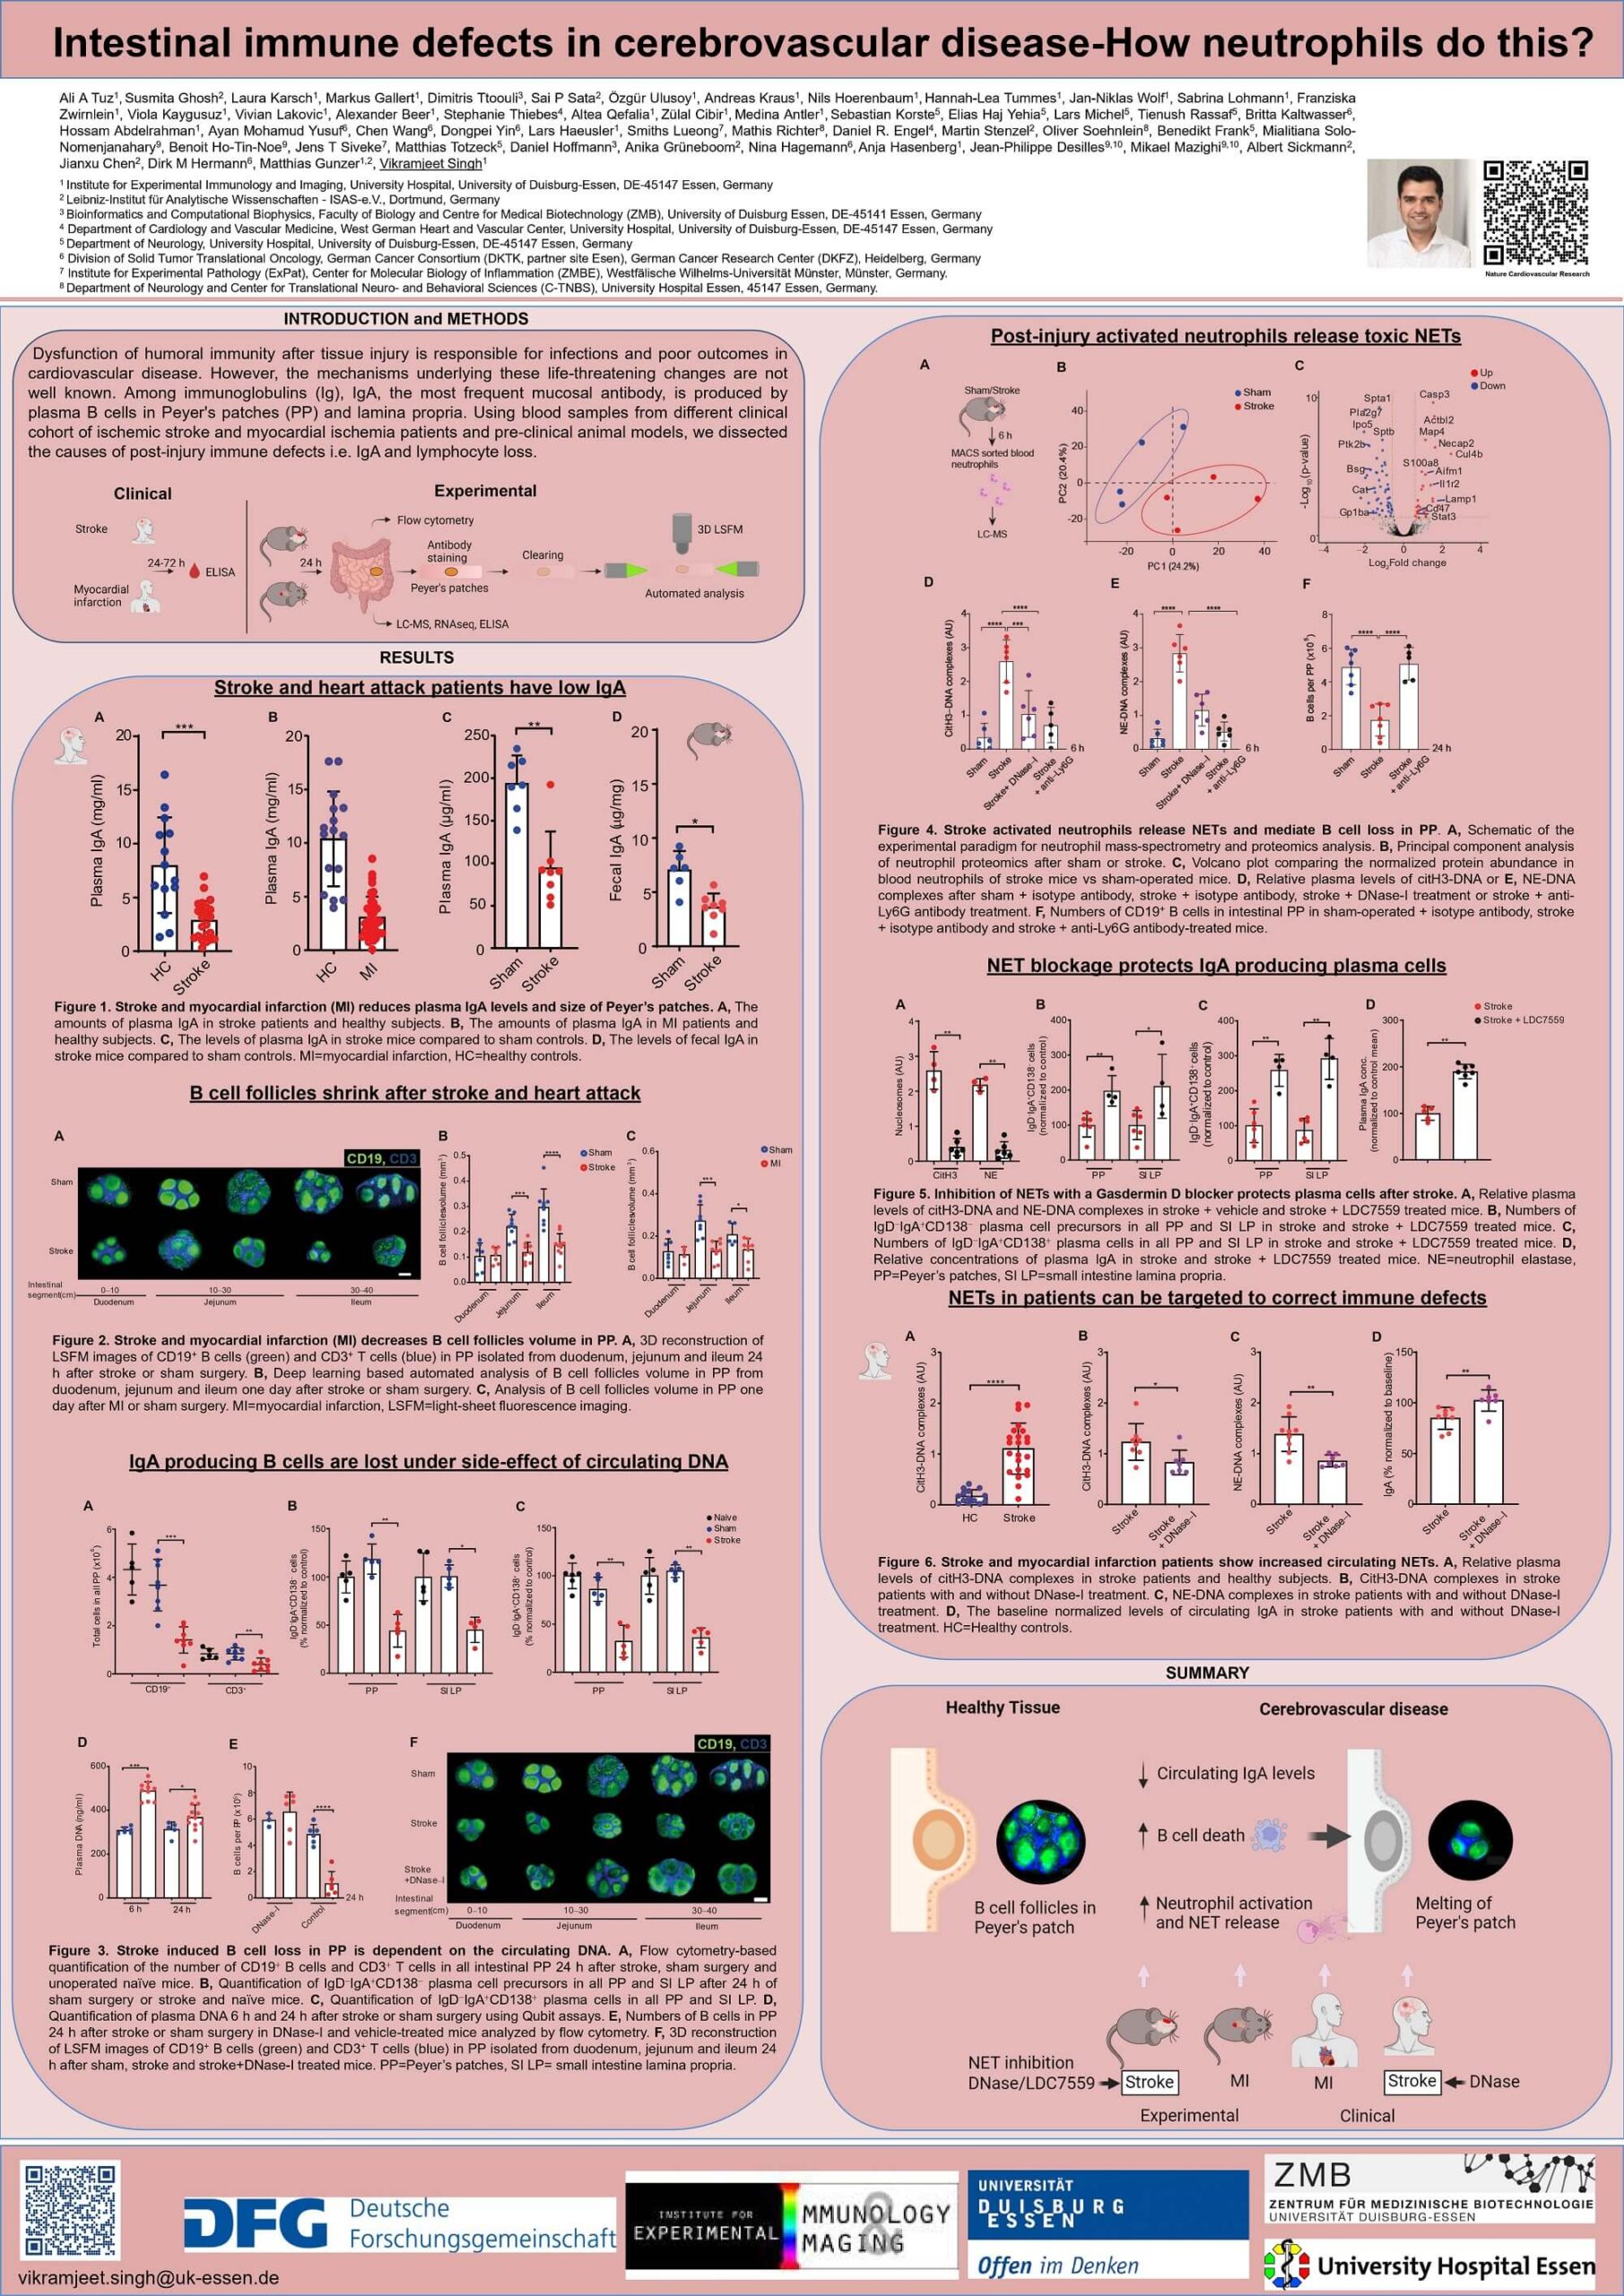

2. Tuz A, Hoerenbaum N, Ulusoy Ö, Ahmadi A, Gerlach A, Beer A, Kraus A, Hasenberg A, Hagemann N, Hermann D, Gunzer M, Singh V. Hypercholesterolemia triggers innate immune dysbalance and transforms brain infarcts after ischemic stroke. Frontier Immunology, 2025 Jan. With DFG funding